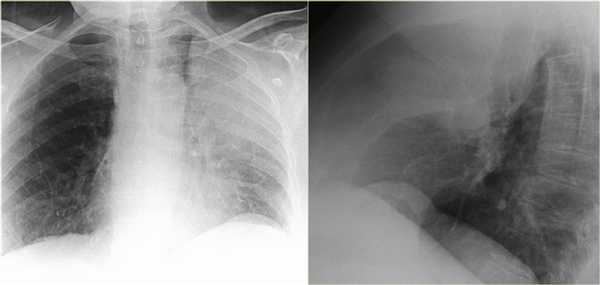

На рентгенограмме органов грудной клетки определяется тотальный ателектаз правого легкого со смещением средостения вправо. На втором снимке представлен тот же пациент, но после лечения. Легкое воздушное и положение средостения в норме. Распространенной причиной тотального ателектаза является неправильно установленная вентиляционная трубка, которая расположена слишком низко и тем самым обтурирует главный бронх.

На ниже представленном снимке представлен пациент с тяжелой бронхопневмонией и тотальным ателектазом. Причиной ателектаза явилось обтурация бронха слизью. После отсасывания мокроты аэрация левого легкого была восстановлена.